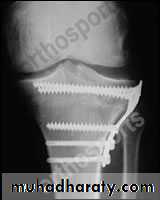

If the above procedure is not applicable we do corrective osteotomy and we should avoid injuring the nearby epiphysis; for varus deformity we do high tibial osteotomy, & for valgus deformity we do supracondylar femoral osteotomy.

• Surgery may be in the form of epiphysial growth arrest (stappling) or by osteotomy.

• Realignment osteotomy; to correct varus deformity we do wedge resection valgus osteotomy of the upper tibia, this acts by

• • Redistribution of weight towards more healthy areas of the articular cartilage.

• • Venous decompression to decrease pain.

• • Correct deformity.